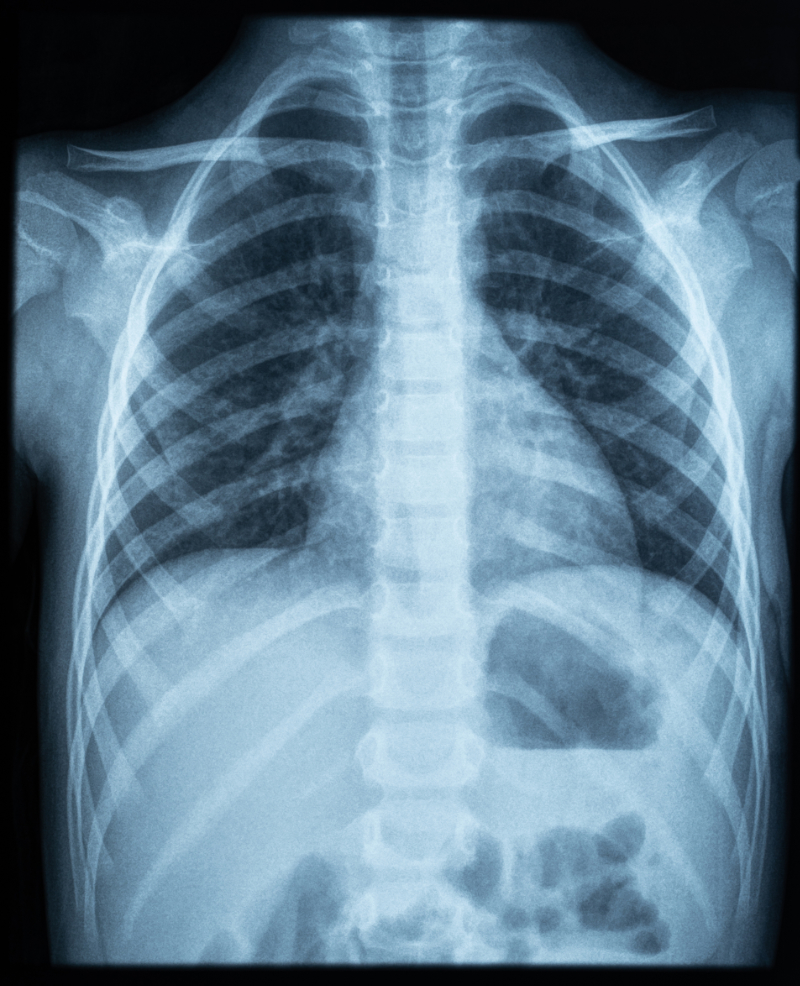

Upon assessment, Mr. Jamison appears anxious and is in respiratory distress. His respiratory rate has increased to more than twenty breaths per minute, and he has decreased breath sounds on the right side of his chest. His oxygen saturation is 88% on room air. A chest X-ray is ordered, which reveals a large right-sided pneumothorax with mediastinal shift.

Mr. Jamison's chest X-ray is repeated after 48 hours, showing re-expansion of the lung and resolution of the pneumothorax. The chest tube is subsequently removed, and Mr. Jamison is discharged with instructions for follow-up care and smoking cessation support.

Had the X-ray not been completed, the pneumothorax may have been missed, leading to the patient's condition deteriorating. Because no other trauma was involved, such as in the case of a car accident or penetrating trauma, the healthcare provider can possibly take more conservative approaches, such as avoiding surgery.

The first radiologic tool is a chest X-ray.

Chest X-ray